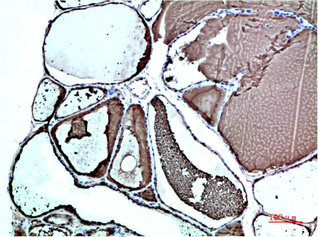

產(chǎn)品描述:TTR單克隆抗體(CUSABIO貨號(hào):CSB-MA263346)是經(jīng)重組蛋白免疫原制備的小鼠IgG型科研用抗體,專用于人源轉(zhuǎn)甲狀腺素蛋白的精準(zhǔn)檢測(cè)。該蛋白作為甲狀腺激素和視黃醇結(jié)合蛋白的載體,在淀粉樣變性發(fā)病機(jī)制研究中具有重要價(jià)值,其異常沉積與家族性淀粉樣多發(fā)性神經(jīng)病變密切相關(guān)。產(chǎn)品采用液體形態(tài)保存,建議長(zhǎng)期存放于-20°C或-80°C環(huán)境以保持穩(wěn)定性,適用于ELISA、Western Blot和免疫組化三大實(shí)驗(yàn)平臺(tái)。在蛋白質(zhì)相互作用分析、病理切片中TTR分布定位、以及疾病模型構(gòu)建等基礎(chǔ)研究中,該抗體可有效檢測(cè)內(nèi)源性TTR表達(dá)水平,為神經(jīng)退行性疾病和代謝紊亂研究提供可靠工具。通過(guò)優(yōu)化實(shí)驗(yàn)條件,該產(chǎn)品在膜轉(zhuǎn)印檢測(cè)中展現(xiàn)良好的特異性,適用于檢測(cè)分子量約15kDa的TTR蛋白,滿足科研人員對(duì)轉(zhuǎn)甲狀腺素蛋白功能驗(yàn)證、表達(dá)譜分析及信號(hào)通路研究的多元化需求。

應(yīng)用范圍:ELISA,WB,IHC

Application Recommended Dilution WB 1:500-1:5000 IHC 1:50-1:500 -